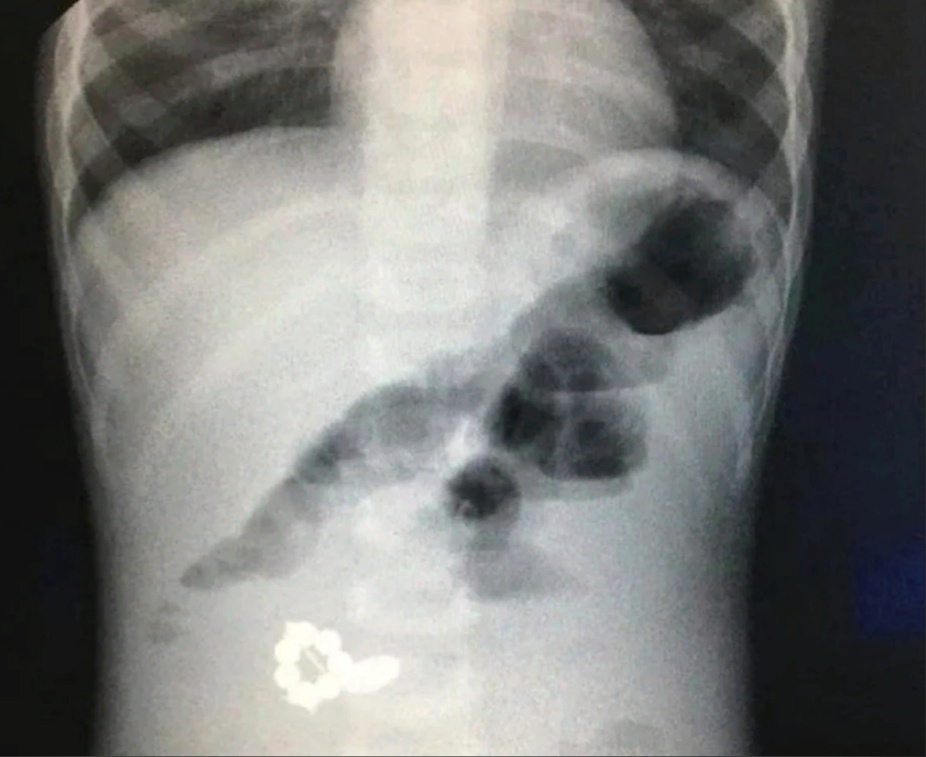

В детскую областную клиническую больницу две недели назад поступил 18-месячный пациент с жалобами на рвоту, вялость и повышенную температуру. Как сообщает министерство здравоохранения региона, для обследования малышу пришлось сделать рентген.

Оказалось, что в брюшной полости у ребенка находились семь магнитов и батарейка. Инородные предметы в организме привели к кишечной непроходимости. Ребенку сделали операцию, которая продлилась 1,5 часа. В настоящий момент маленький пациент чувствует себя хорошо и готовится к выписке.